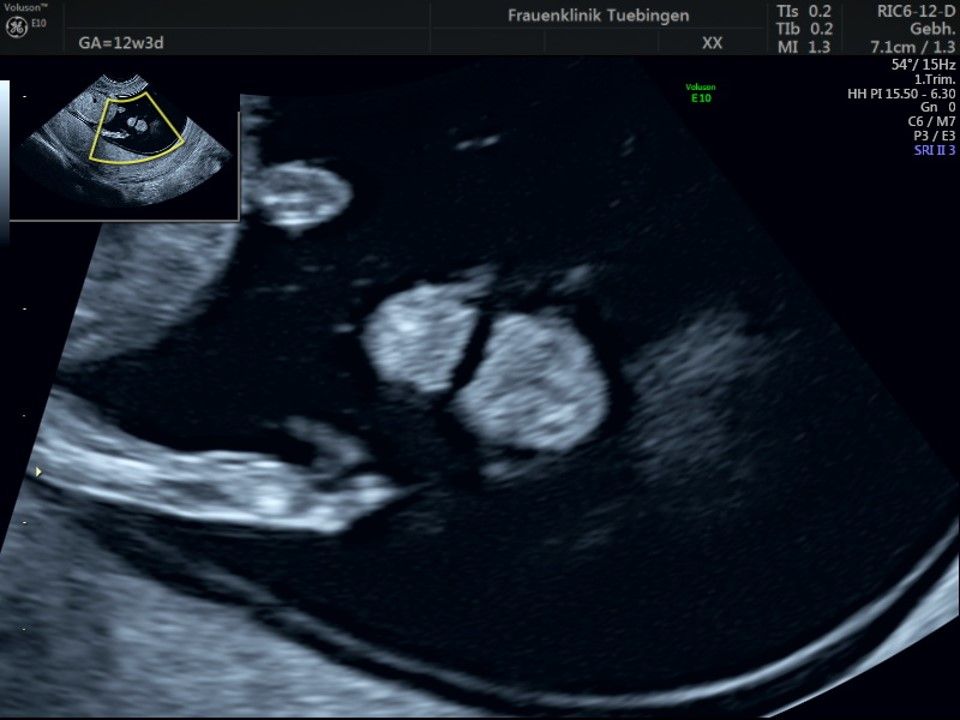

Im Rahmen des Ersttrimester-Screenings untersuchen wir die Organe des Feten mittels Ultraschall. Dabei machen wir auch gerne ein Bild für Sie.

Obwohl der Fet zu diesem Zeitpunkt erst zwischen 5 und 8cm groß ist, lassen sich bereits etwa die Hälfte aller schwerwiegenden Fehlbildungen erkennen bzw. ausschließen. Sollten wir eine Auffälligkeit sehen, werden wir mit Ihnen den Befund und das weitere Vorgehen ausführlich besprechen.

Herz